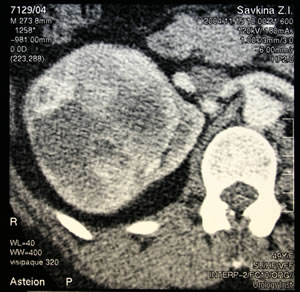

КТ

органов брюшной полости, забрюшинного пространства: |

|